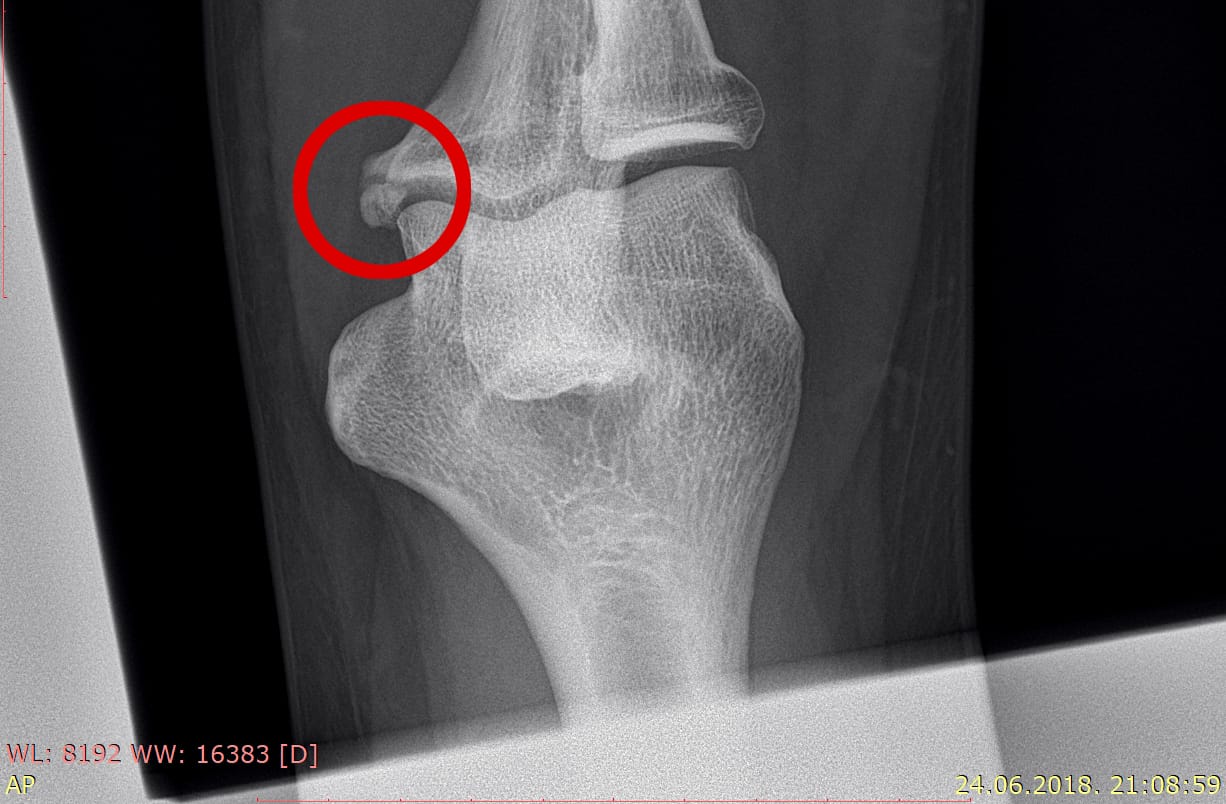

A kako će Surać završiti u zatvoru, sada je jasno i pravnim laicima. Naime, Suraćev odvjetnik Ive Brkić, koji je RTG snimku loma Bajlove ruke dobio tako što mu je istu ilegalno dostavila zadarska bolnica (o tome u daljnjem tekstu, op.a) dao je na vještačenje dvojici privatnih vještaka koji su utvrdili kako se na snimci ne vidi prijelom. Temeljem takvog “novog dokaza”, sutkinja Teodora Projić Škovrlj dopustila je obnovu procesa unatoč izričitom protivljenju ODO-a kao tužitelja u ovom predmetu. Na kraju su RTG snimku dobili, ona je sada dio predmeta i na prvom ročištu ista ta RTG snimka bit će vještačena, najvjerojatnije od strane nekog od medicinskih fakulteta. Onoga trena kad se dobije mišljenje medicinske institucije kako se na snimci vidi prijelom, odnosno teška tjelesna ozljeda, Surać ide na izvršenje zatvorske kazne i tu priča konačno završava. (

Na slic se nalazi RTG snimak na kojemu se vidi lom Bajlove ruke)

Do RTG snimke loma Bajlove ruke došli su nelegalno. Unatoč tome, na snimci je itekako vidljiv prijelom pa će Surać morati u zatvor Temeljem vještačenja iz kojega proizlazi kako vještaci Potočki i Škavić na RTG snimku ne vide prijelom, a koji je vidljiv i običnom laiku, od Općinskog suda u Zadru Ive Brkić traži obnovu postupka. Zatražio je odvjetnik Brkić i odgodu izvršenja pravomoćne presude. Nakon toga, Brkić se obraća Općoj bolnici Zadar i traži na uvid RTG snimak loma Bajlove ruke što mu bolnica, točnije Vedrana Vitlov, magistrica prava i omogućava.